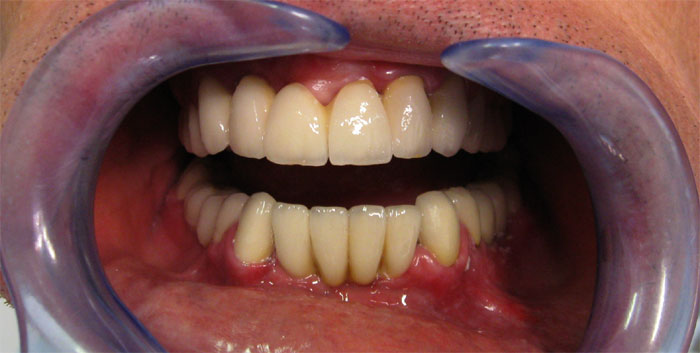

Nachfolgend finden Sie Fotos und Interview-Videos von Patienten, die in der Klinik Europa Dental implantatgetragene Brücken haben machen lassen.

Fall Nr. 1: Brücke auf Alpha-Bio-Implantaten und Brücke auf natürlichen Zähnen